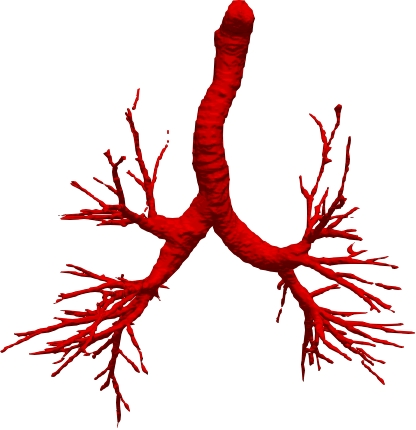

However, current state-of-the-art methods of lung organ segmentation still face several challenges and aspects for improvement. Firstly, the unlimited voxel values, multi-site imaging discrepancy and class imbalance in lung organ images can lead to false-negative and leakage issues in prior segmentation methods, which badly influences the critical early diagnosis of imperceptible lung diseases, e.g., lung fibrosis, nodule and hypertension, etc. Secondly, the presence of numerous slender branches, e.g., bronchioles and arterioles, which are easily lost during the recycled down/up-sampling procedure in Fig. 1, can result in discontinuity, detail loss, and coarse mask predictions. Thirdly, most CNN-based medical segmentation methods treat all points equally during the mask rendering stage, overlooking the vulnerability of border points in Fig. 1 (f) and the importance of explicit border modeling. Lastly, while Vision Transformer (ViT) has shown promise in computer vision tasks [1, 4], its quadratic operation complexity limits its application in 3D high-resolution CT images due to hardware constraints. Meanwhile, most specific datasets for medical image analysis are small and scarce due to laborious manual annotation and privacy protection, which badly restricts the potential of transformer-based top-tier methods.

2.2 Global-Local Cube-tree Fusion

To the best of our knowledge, most mask render-based two-stage semantic segmentation methods [6, 21] operate equally on all dense points of the coarse masks to improve the final performance, which is unnecessary to focus much on the already correctly predicted points. As shown in Fig. 1 and according to our statistical error analysis, most very vulnerable points occur on the object border due to the information loss caused by down-sample operation in the encoding process, especially for the innumerable bronchioles or arterioles in the tree-like structures. Thus, we only focus on the border vulnerable points and propose the novel global-local cube-tree fusion module. Specifically, (1) we “recycle” the down-sample and up-sample operations to produce masks and , and evaluate the absolute difference of them in Fig. 1 to get the border vulnerable points for the -th layer; (2) as shown in the top-right side of Fig. 2, we build the cube-tree of the -th point by extracting the local contextual features of {26, 27}-neighbors of the {, +1}-th layers respectively, which are defined as the cube without and with centroid. For the last layer, it is of note that we extract the 27-neighbors’ local contextual features in the adjacent layer -1; (3) we flatten features in the spatial dimension and project them as well as centroid feature into three vectors , which are separately related to the fine grain, coarse grain local context information and cube-tree centroid feature; (4) global airway or artery features from the distribution of the whole dataset is also very important, hence, we introduce the learnable global features to yield the projected global features , where is the embedding dimension; (5) we fuse the four features into as follows:

where [0, 1] are the learnable coefficients to balance the importance of each feature; (6) we lastly add the feature to the relative position embedding features (retaining the topology information for inductive bias) for the voxel-wise decoding and refined prediction. Obviously, our proposed global-local cube-tree fusion module focuses merely on all border vulnerable points in Fig. 1(f) rather than all regular dense points in Fig. 1(c), which is more related to the lung organ regions. Experimental results demonstrate the efficacy of this design.

We qualitatively analyze our method on four challenging lung organ datasets. In Fig. 5, SFCN [19] suffers from severe false positives and some false negatives, especially for the big green areas of airway leakages. WNet [22] is mainly influenced by false negatives on the main trachea. For the Fibrosis dataset at the third row, it also encounters the false negative problem in the terminal bronchioles moderately. FANN [10] bears the slight discontinuity issue of false negative in the terminal bronchioles of BAS dataset, and the severe discontinuity and airway leakage problems on the more challenging Fibrosis benchmark. Instead, due to the above two novel modules, our method can solve the defects of false negative, discontinuity, and leakages faced by past advanced methods. Besides, the results on PARSE22 artery dataset in supplementary Fig. 6 also proves this.